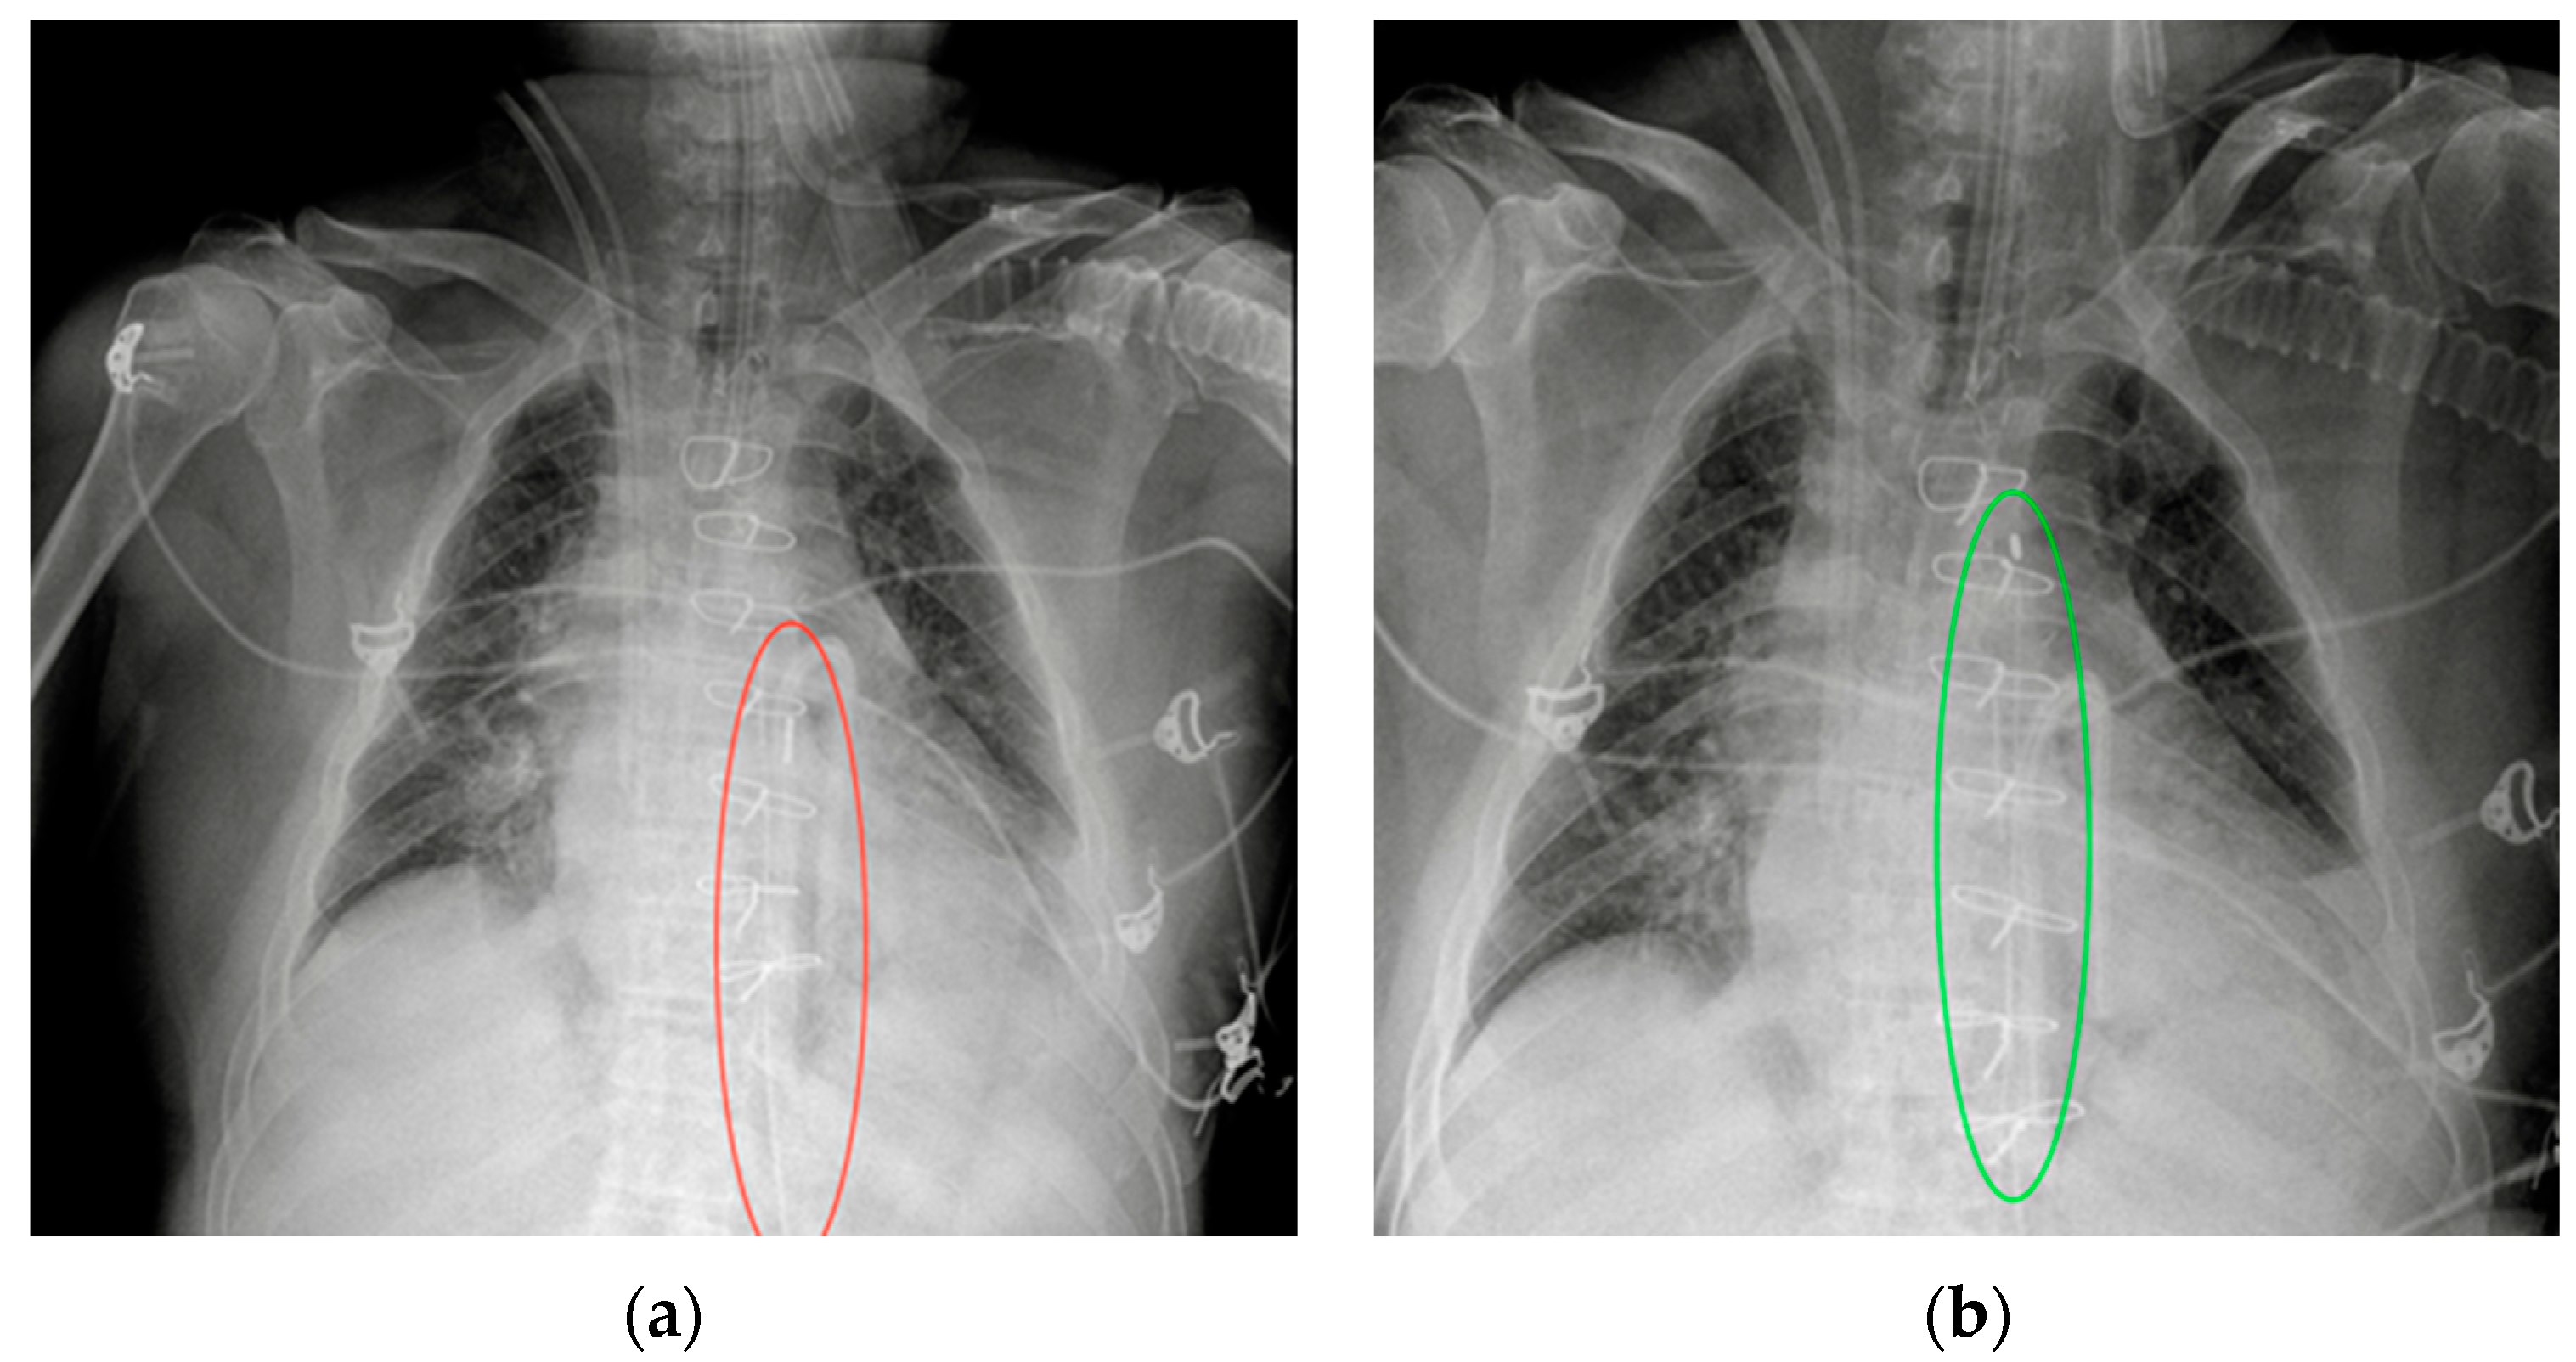

5.2. Pacemaker (PM) and Automatic Implantable Cardioverter-Defibrillator (AICD)

| PM and AICD | Leads misposition/breakage |

| Twiddler’s syndrome | |